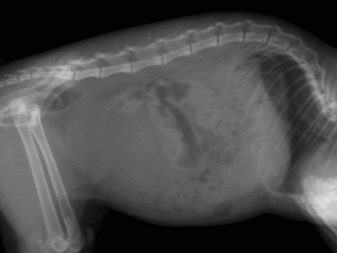

The characteristic and only genetic disease of short-footed cats is presented as lordosis of the vertebral part of the skeleton. With such a defect, pets can suffer stretching in the thoracic region. This pathology can also provoke additional diseases. Usually they concern the internal organs. The heart and lungs become the most vulnerable.

Lordosis

At risk are animals with different genetic abnormalities. Also, lordosis can hit a cat with obesity. For this reason, you need to carefully monitor the diet of the animal. It is strictly forbidden to overfeed him and deviate from the recommendations related to food.